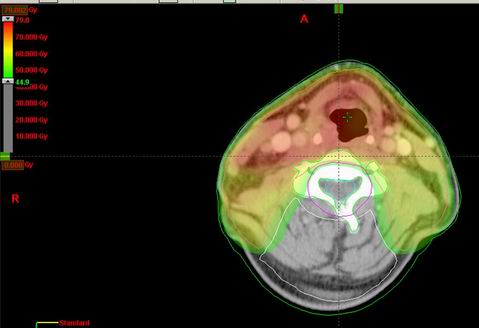

53-letý Z.T.

Karcinom hypofaryngu, recesus piriformis l.dx T2 N2b M0, spinoca

Kurativní RT – konvenční frakcionace

Zakreslení struktur:

DVH:

Dávka > 40Gy:

Dávka > 45 Gy:

Dávka > 54 Gy:

Dávka > 60 Gy:

Dávka > 72 Gy: